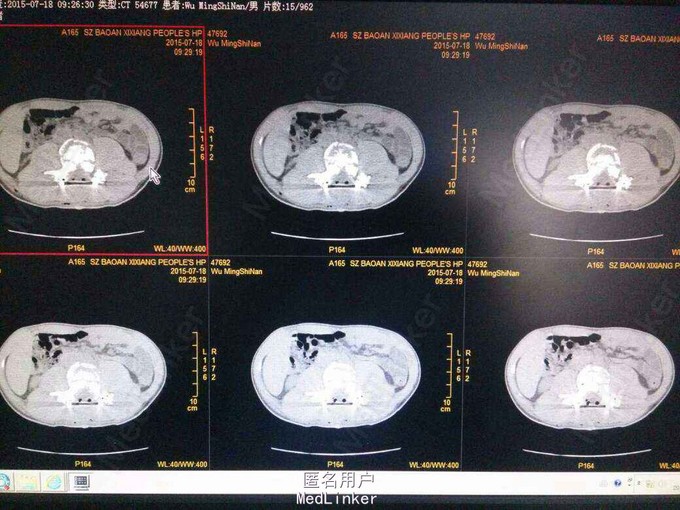

腰3椎体爆裂性骨折并双下肢不全瘫 手术后路椎管减压,椎弓根固定,腰3椎体骨折复位,后外侧植骨,椎管探查,硬膜修补。 术后脱水,激素,神经营养,二便及下肢功能康。 术后影像表现腰3椎体后移骨块复位。

一周后小便可自解,肌力:胫前:左III,右4级。 腰椎骨折后路減压可达到理想效。